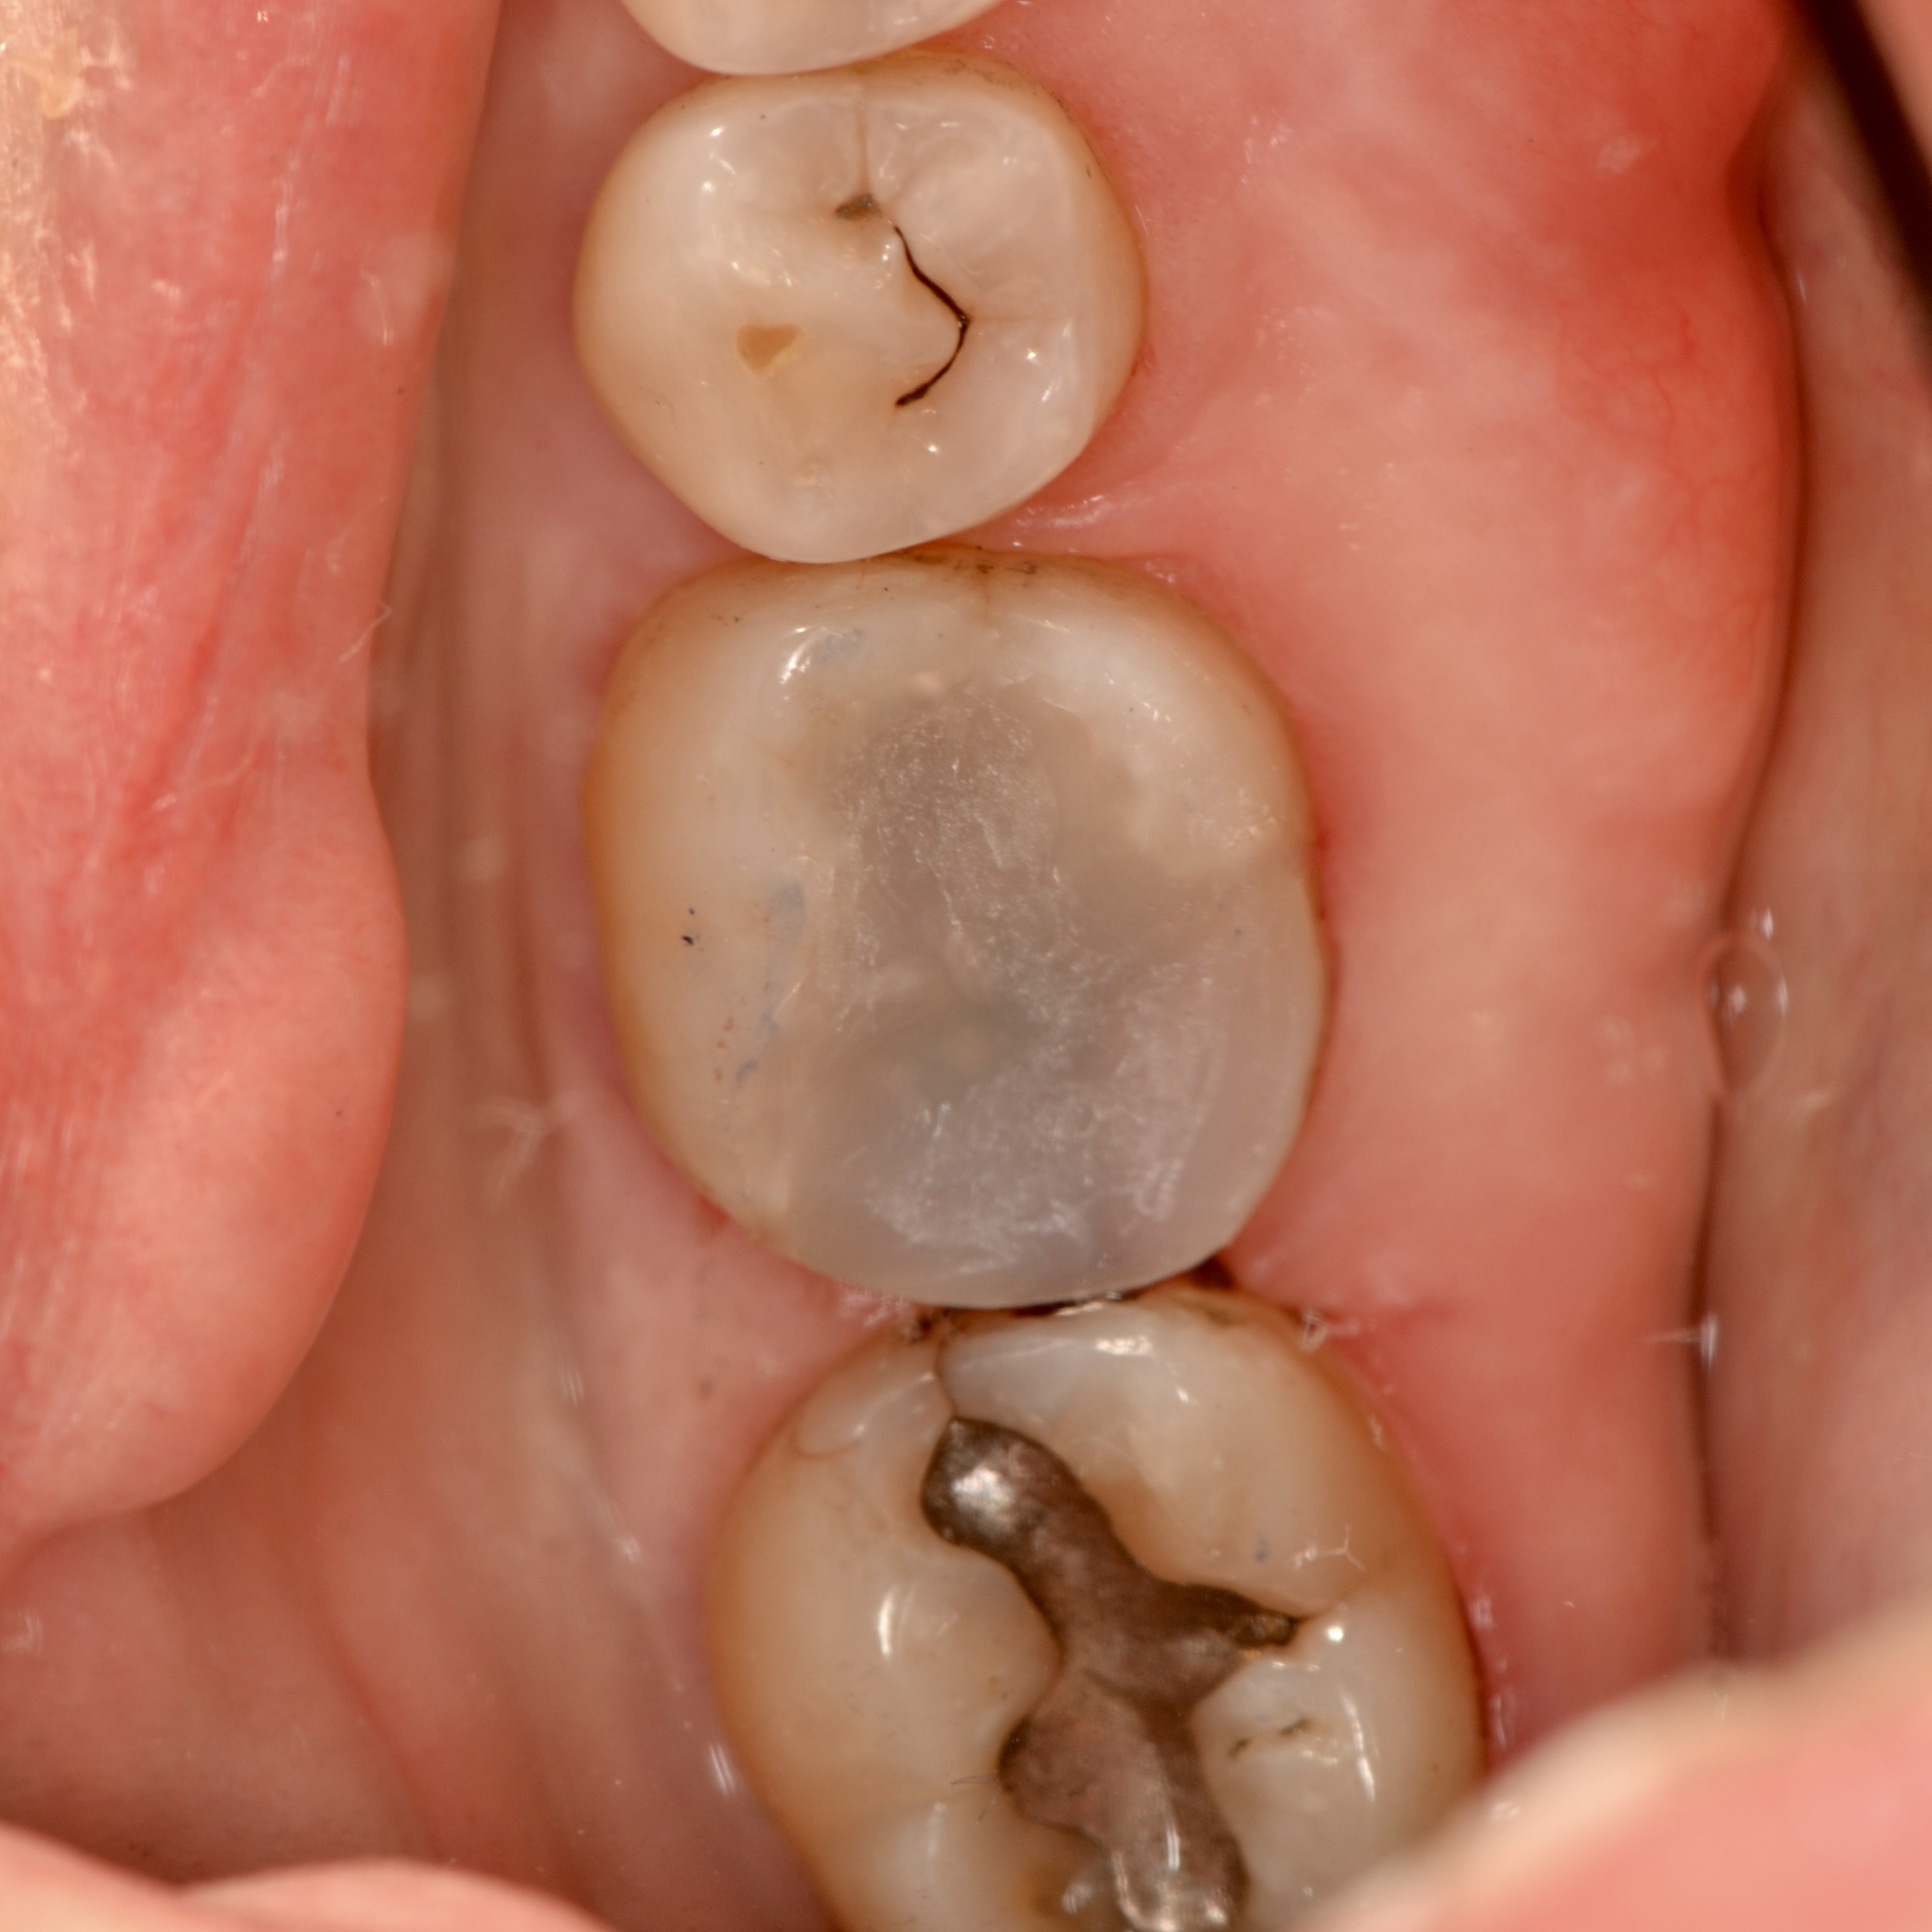

Cavity Broken Metal Filling